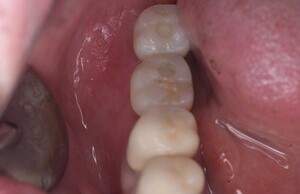

口腔内写真

- Befor

- After

| 年齢 | 50代・男性 |

|---|---|

| 主訴 | 部位:左下6番7番 主訴:左下奥歯腫れて痛い。 |

| 治療内容 | 左下6番抜歯、左下6番7番骨造成、インプラント埋入 |

| 治療費 | 合計:1,232,000円 ・内訳 診断料:55,000円 サージカルガイド2本:66,000円 GBR:110,000円×2本 埋入料:165,000円×2本 静脈内鎮静麻酔:77,000円 2次OPE:22,000円×2本 仮歯:55,000円×2本 上部構造(フルジルコニア):165,000円×2本 (2023年1月現在) |

| 治療期間 | 約8ヶ月 |

| リスク・副作用 | リスク・副作用 |

| 治療方針 | 元々支台歯に負荷がかかりやすいとされている延長ブリッジを抜歯し、1本単体でしっかりかめるようにインプラントを2本埋入した。骨吸収も進んでいたため、※GBR法で骨造成を同時に行った。 治療と並行して、全顎的な歯周病治療も行い、今後は歯周病が進行しないよう、こまめにメンテナンスに通っていただく。 |

| 特記事項 | ※1 GBR・・・骨再生誘導法。骨の高さや厚みを人工骨や人工膜などを使用し再生する方法 |

| 担当者所見 | 6番は歯根分割された被せ物が7番の欠損部との延長ブリッジとされており、強い咬合と歯周病も相まって負荷がかかり動揺し、歯として機能しなくなったため、抜歯となった。 |